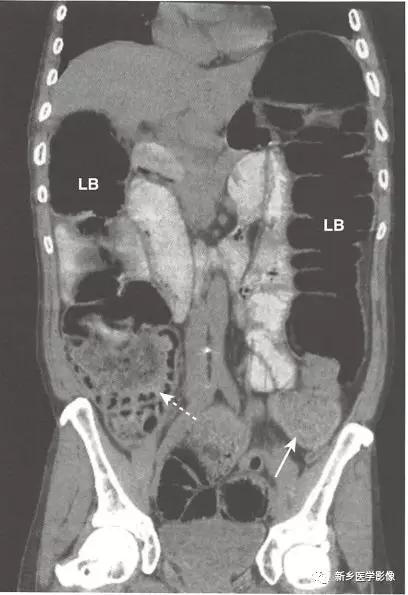

机械性肠梗阻:大肠梗阻(LBO)

1、病理生理学: 存在一种结肠内部或外部的病变阻塞肠腔。随着时间推移,结肠将从梗阻点逆行扩张,即使梗阻最远端位于乙,状结肠,盲肠也通常在扩张的结肠中直径最大。

大肠正常具有吸收水的功能,所以在梗阻的结肠中很少见到或没有气-液平面。随着时间推移,持续的蠕动波将推动梗阻远端的结肠内容物向前移动至排出。在机械性大肠梗阻中,在直肠中通常很少见到或没有气体影。

2、机械性大肠梗阻的关键的影像学特征

梗阻近端结肠扩张。

由于大肠肠襻数目有限,且不互相重叠(如小肠肠襻),所以有时可以通过观察最后含气的结肠肠段来确定梗阻部位。

不论肠梗阻部位在何处,盲肠往往是结肠的扩张最严重的肠段,当盲肠直径达到15cm以上时,须警惕盲肠破裂的风险。

小肠不扩张(除非回盲瓣功能不全)。

因为直肠常常位于梗阻部位以远,所以直肠内包含很少气体或没有气体。

由于大肠具有重新吸收水的功能,大肠内通常没有或很少气-液平面。

4、在CT上辨识大肠梗阻

CT可用来确定梗阻原因、评估是否存在腹腔游离气体以及明确相关并发症,如肝脏或淋巴结转移等。

在梗阻部位近端大肠肠腔扩张,在梗阻部位远端肠腔直径恢复正常。

梗阻处通常是结肠癌造成,在CT上表现为软组织肿块,累及大肠的疝也很容易在CT上显示。